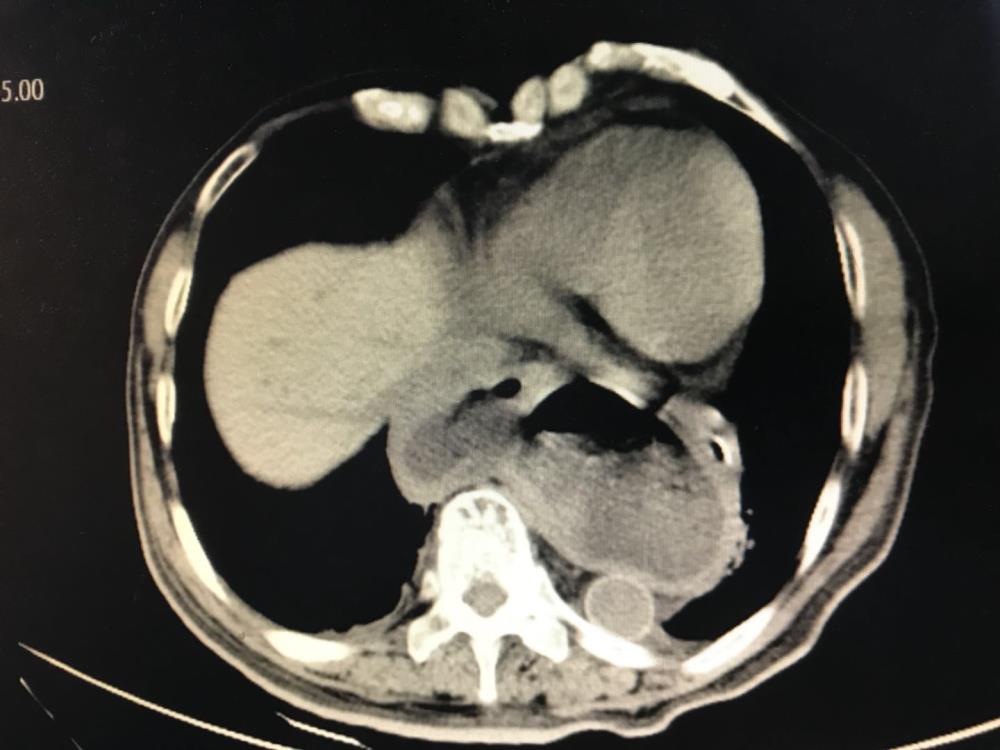

患者吴某,男性,81岁,20年前出现进食后频繁呕吐伴反酸、烧心,于多地多家医院求医,予促胃动力药、治酸药物等对症处理,症状稍有改善,但病情反复,此次因急性进食后呕吐不止,反酸、烧心收住我院消化内科,我院CT提示:食管裂孔疝嵌顿,遂请我院胃食管反流诊疗中心副主任、疝与腹壁外科杨越涛副主任医师会诊,予查上消化道造影、食道测压等检查,由于患者病史时间较长,导致其营养状态极差,经充分讨论决定由杨越涛副主任医师为其主刀行腹腔镜下食管裂孔疝无张力修补+食管后方360度Nissen胃底折叠术,术中出血不到30ml。患者术前呕吐、反酸十分明显,一度不能进食,然术后第一天就下床活动,恢复进食,呕吐与反酸症状消失,疗效显著。

患者李某,78岁,8年前于某省级医院行胃癌毕I式根治手术,术后出现严重反酸、烧心,于多地多家医院求医,曾多次被误诊为冠心病等其他疾病,治疗后无明显改善。看过我院胃食管反流疾病诊治中心的报道,感觉自身症状与胃食管反流病相似,遂来我院胃食管反流门诊就诊,经过中心副主任陈小燕副主任医师、夏宣平副主任医师,疝与腹壁外科杨越涛副主任医师等共同会诊,经胃镜、食管测压、上消化道造影等检查后确诊为:1、胃食管反流病2、食管裂孔疝(滑动性)3、胃癌根治术后(毕Ⅰ式)、残胃炎、吻合口炎,有明确手术适应症。经过充分术前准备后,由杨越涛副主任医师主刀在腹腔镜下通过1个1.2cm,1个1.0cm和3个0.5cm小孔行食管裂孔疝无张力修补+食管前壁90度胃底折叠术,因患者曾行胃癌根治性手术,再次手术难度大,在我院胃肠外科专家在沈贤副院长现场指导下,仔细分离腹腔黏连,暴露残胃、食管下段与疝内容物,予关闭裂孔疝并放置专用补片预防复发,术中仅出血50ml。患者术后第一天拔除胃管,恢复流质进食,自行下床活动,术前反酸、烧心症状得到完全改善。